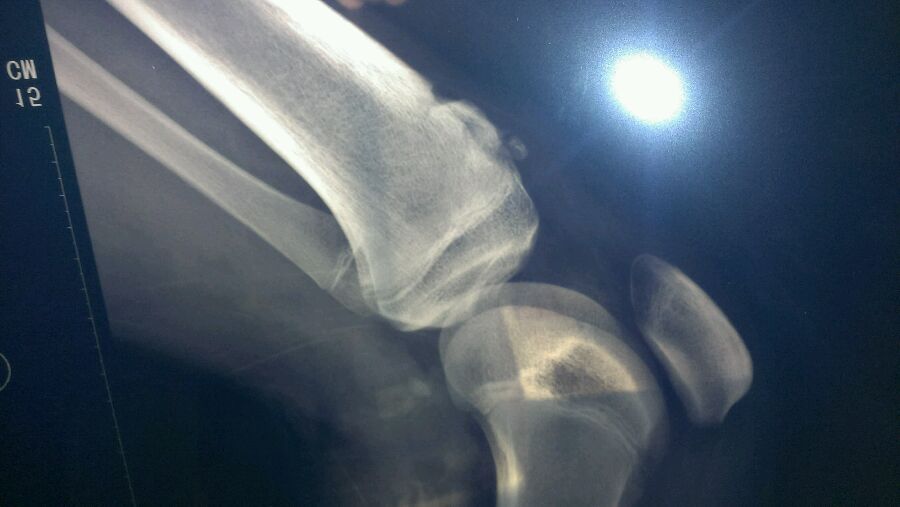

从初二就开始有了(一开始没这么高),现在高一了,有一次又被同学撞倒,这个部位狠狠得撞在了地上,然后就发现比以前更疼了,而且更难恢复,求医生支招, 顺便问一下,护带这样绑可以吗?